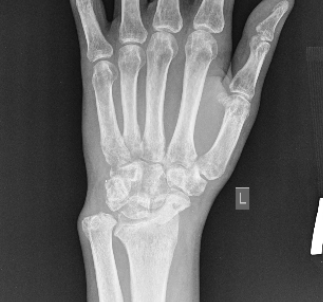

Soft tissue contracture prevented reduction of the dislocation. On March 18, 2022, resection of the proximal row of carpal bones was performed, as well as resection of a fragment of the styloid process of the left radius with fixation of the hand and forearm in the Ilizarov frame (Fig. 5).

| Fig. 5 AP and lateral radiographs taken on day 1 Fig. 6 Treatment result. AP and lateral radiographs post-surgery at 1-year follow-up |